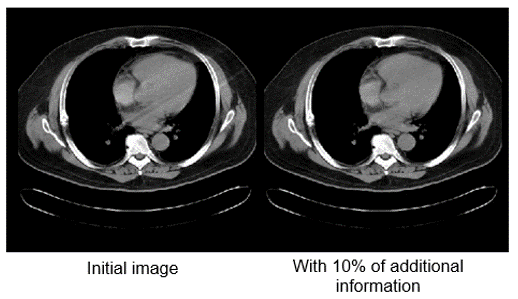

Iterative reconstruction and denoising techniques facilitate CT radiation dose reduction because they reduce image noise, which is one of the limiting factors of dose reduction.

Motion artifacts can be reduced by using special reconstruction techniques. 10% is added to the 360-degree standard rotation. Repeated projections are averaged which reduces motion artifacts. The image on the left shows less motion when this technique is used.